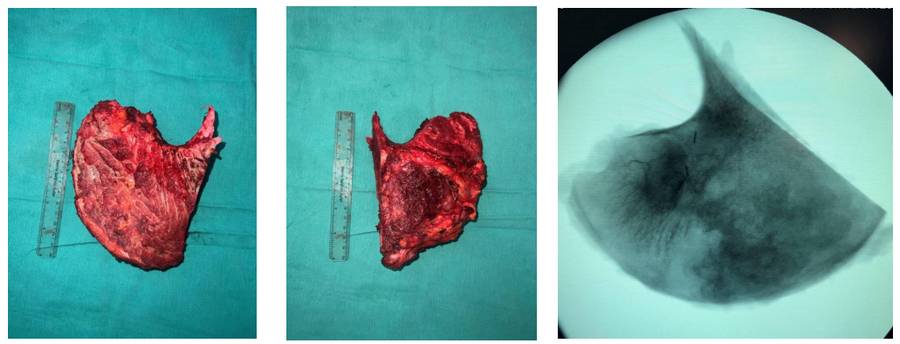

Ameliyat Esnası: Çıkarılan tümör dokusunun klinik ve skopi görüntüsü